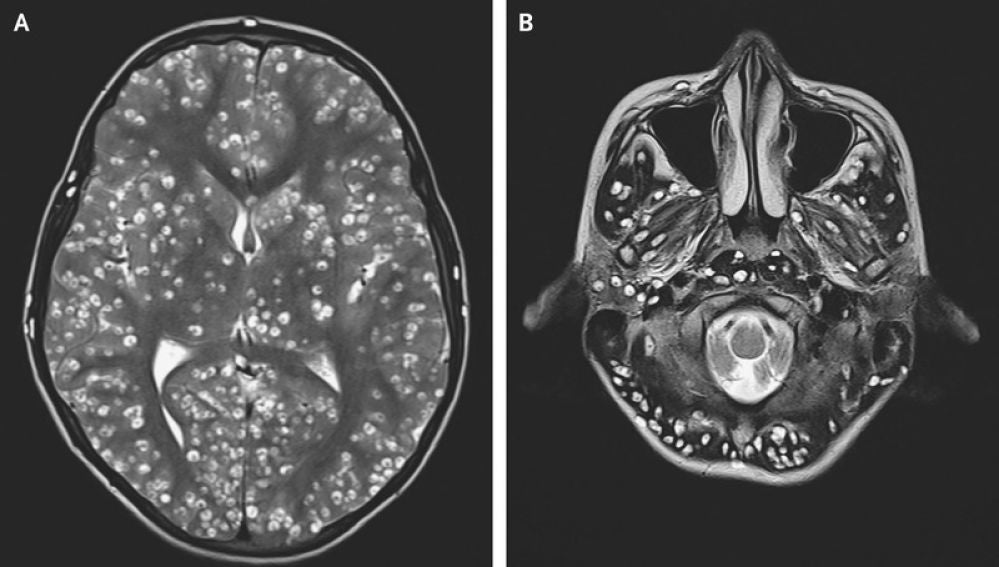

Cerebro del joven infectado con gusanosNew England Journal of Medicine

La joven se sometió a una operación para extirpar el tumor. Durante la cirugía el neurocirujano vio "una lesión bien encapsulada y firme que era ovoide". "Parecía un huevo de codorniz", afirma Rasouli. En ese momento el médico descubrió que no se trataba de un tumor cerebral. El doctor cogió una muestra de la lesión extraída, la colocó bajo un microscopio quirúrgico y descubrió que lo que tenía era una tenia de cerdo.